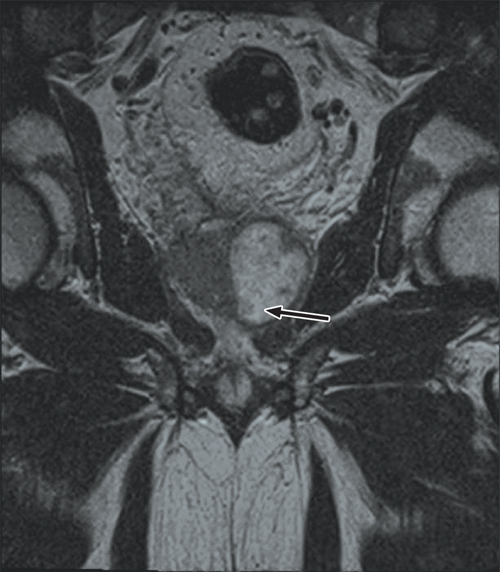

Further questioning found that the patient had a recent history of travel to South-East Asia and previous use of fluoroquinolone antibiotics. He was treated with intravenous cephazolin but his temperature continued to spike above 38°C. Magnetic resonance imaging (MRI) of his pelvis revealed a large prostatic abscess (Box 1), which was drained by transurethral resection. Tissue culture was consistent with the MDR E. coli previously isolated.